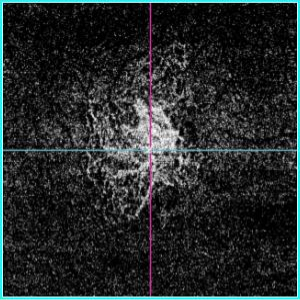

OCTアンギオグラフィー(OCTA)

造影剤を用いることなく、網膜・脈絡膜血管内の血流の様子を可視化することができます。